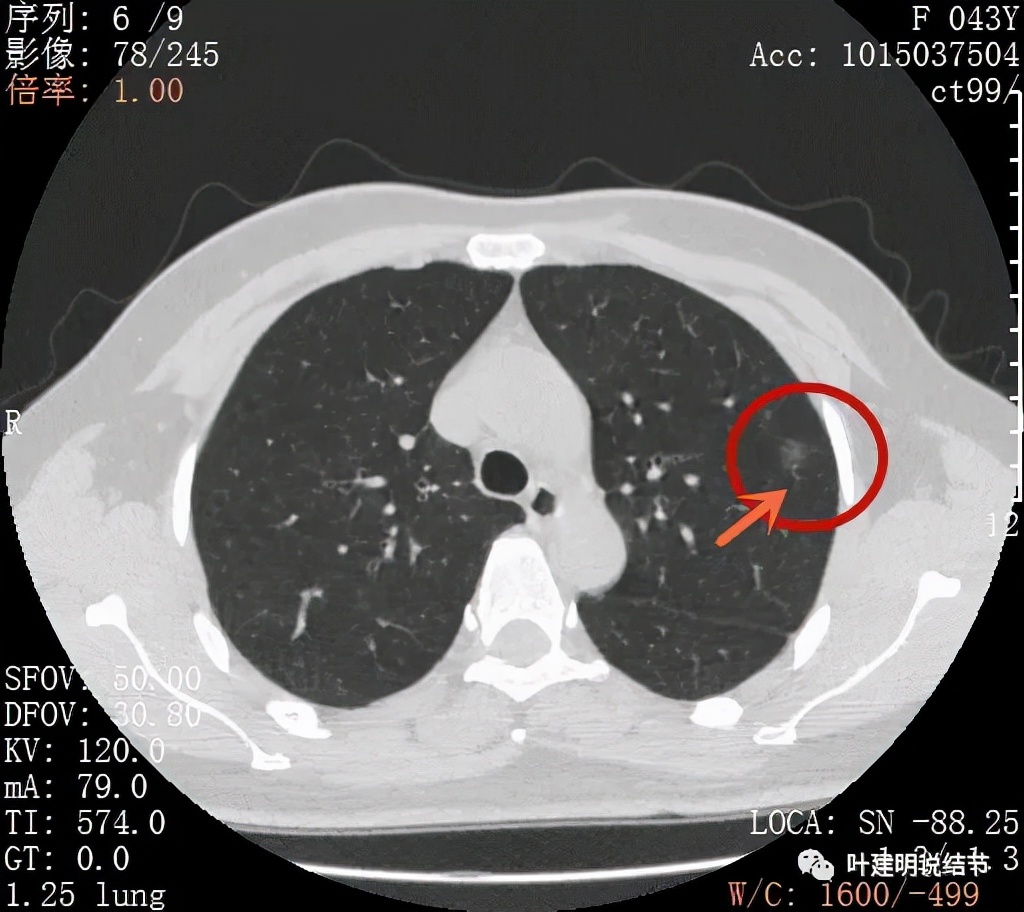

病灶密度较低,膨胀性略,瘤肺边界在靶扫描上还是显得有些清晰的

病灶瘤肺边界清,密度偏低,有点散,但有微小血管进入(桔色箭头)